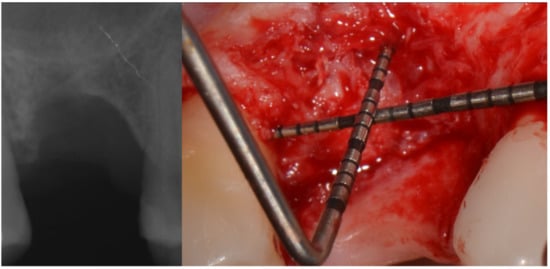

The bone lamina was shaped as a saddle, fixed to the buccal bone with two pins, and then, after the area was grafted with a mix of autogenous bone and collagenated xenograft (50–50%), reflected and stabilized under the palatal flap (Figure 7). Flaps were secured with 4.0 resorbable sutures and healing was uneventful.

Figure 7.

Bone lamina in place, arrows indicate the thickness of the lamina (1 mm) inducing both GBR and GTR effect.

Three months after extraction the site was approached by means of GBR with the cortical lamina technique. Two periodontal probes were crossed to measure 7 mm of the vertical component, and 13 mm of the mesio-distal extension from bone peak to bone peak (Figure 6).